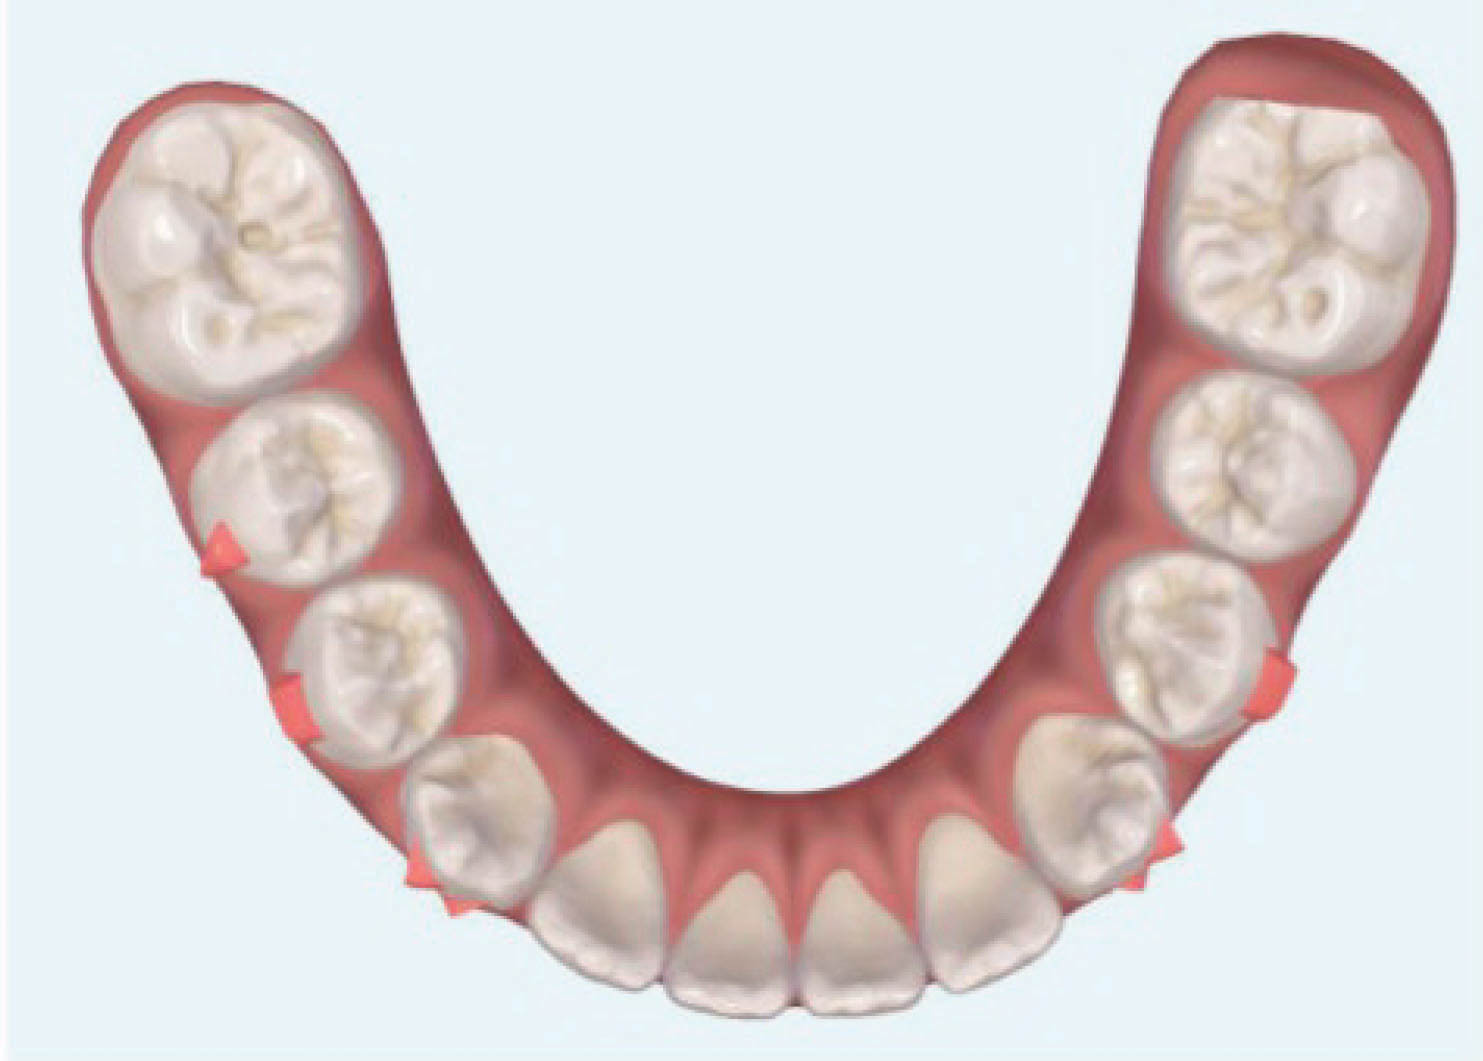

بیمار دیگر (شکلهای 50-6 الی 52-6): لترال چپ بالا را ندارد. هدف دیستاله نمودن کانین چپ بالا و هدایت آن تا رسیدن به رابطه کلاسI کانینی و نهایتاً قرار دادن یک ایمپلنت در ناحیه لترال است. اگر به OPG او نگاه بندازید، میبینید که لترال چپ بالا وجود ندارد و لترال راست بالا هم peg shape است.

: باید به لابراتوار بگوییم که تیپ دیستالی بیشتر به ریشه کانین چپ بالا بدهد. این زاویه بیشتر برای بیومکانیک کار است تا دندانها تیپ نشوند. باید در این بیمار هم همین کار را انجام داد. از آنجایی که قرار است کانین چپ بالا دیستالی بشود، احتمال دیستالی شدن تاج و مزیالی شدن ریشه وجود دارد. این حالت نه تنها مدنظر نیست، بلکه فضای کافی هم برای قرار دادن ایمپلنت به ما نمیدهد. بنابراین باید زاویه بیشتری به ریشه بدهیم تا در نهایت یک حرکت بادیلی داشته باشیم.

در OPG نهایی، کانین راست بالا در جایگاه صحیح است و فضا کافی برای ایمپلنت هم به وجود آمده است (کل درمان ۲۰ ماه به طول کشید). در این بیماران، باید حتماً درمان اضافه را در طراحی کامپیوتری در نظر بگیرید تا حرکتها بادیلی بشوند.